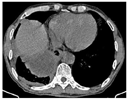

患者肺脓肿并多房包裹性脓胸诊断明确。于11月3日在CT引导下行包裹性脓胸穿刺(图7)及置管引流(图8)术。穿刺处胸水常规:深黄色、微浊胸水,无凝块,白细胞总数29×106/L,单个核细胞31%,多个核细胞69%,红细胞0×109/L,李凡他实验+;胸水生化:白蛋白25.5 g/L,球蛋白17.7 g/L,总蛋白43.2 g/L,淀粉酶40 U/L,葡萄糖7.01 mmol/L,乳酸脱氢酶556 U/L,腺苷脱氨酶17.91 U/L。胸水检验结果支持肺炎旁胸腔积液。置管处胸水常规:黄色、浑浊胸水,无凝块,白细胞总数100803×106/L,单个核细胞15%,多个核细胞85%,红细胞38×109/L,李凡他实验+++;胸水生化:白蛋白26.4 g/L,球蛋白23.6 g/L,总蛋白50 g/L,淀粉酶30 U/L,葡萄糖0.03 mmol/L,乳酸脱氢酶7020 U/L,腺苷脱氨酶130.15 U/L;胸水培养(需氧菌+厌氧菌)阴性;未查见抗酸杆菌。引流出脓性胸水约200ml(图9)。胸水检验结果支持脓胸。复查红细胞沉降率102 mm/h;血常规:白细胞计数11.9×109/L,中性粒细胞绝对值9.15×109/L,血红蛋白103 g/L,中性粒细胞百分率76.9%;C反应蛋白260.45 mg/L;肝功能:白蛋白33.5 g/L,直接胆红素26.2 umol/L,总胆红素32.4 umol/L,总胆汁酸17 umol/L;降钙素原0.69 ng/ml。予生理盐水和碳酸氢钠反复冲洗脓腔、尿激酶(1万U,1次/d)胸腔内注射,同时给予人血白蛋白静脉滴注以纠正低蛋白血症。复查胸部彩超提示右侧胸腔包裹性积液,积液黏稠,周围壁及分隔较厚。复查胸部CT(图10、图11)示:右肺上叶后段、右肺中叶及下叶多发感染并右肺下叶肺脓肿形成,右肺感染较前有所吸收;右侧胸腔引流术后,右侧胸腔积液、积脓较前吸收减少;右侧胸膜增厚。于11月8日再次在CT引导下行包裹性脓胸穿刺术。患者临床症状逐渐改善,11月17日复查红细胞沉降率96 mm/h;血常规:白细胞计数7.89 ×109/L,中性粒细胞绝对值4.53×109/L,血红蛋白104 g/L,中性粒细胞百分率57.4%;C反应蛋白25.75 mg/L;白蛋白40.8 g/L;降钙素原正常。11月22日复查胸部CT(图12,图13):右肺下叶见片状、不规则状密度增高影,部分可见液化坏死,较前片吸收好转;右肺底局限性包裹性积液;双肺下叶、右肺中叶感染;右侧胸膜弥漫性增厚,右侧胸腔包裹性积液;右侧斜裂少许包裹性积液;纵隔淋巴结肿大。11月23日复查红细胞沉降率60 mm/h;血常规:白细胞计数5.57×109/L,中性粒细胞绝对值2.76×109/L,血红蛋白106 g/L,中性粒细胞百分率49.6%;C反应蛋白11.93 mg/L;电解质正常。患者病情好转于11月24日出院,继续口服莫西沙星和甲硝唑抗感染治疗1个月。